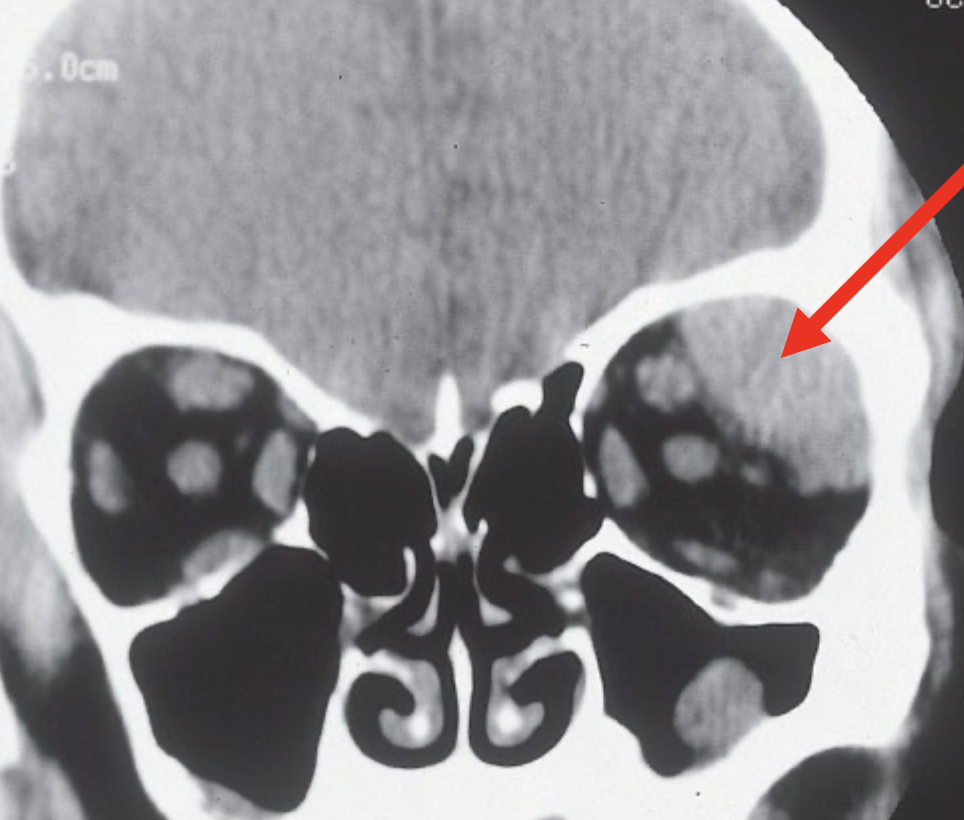

Define pre-septal cellulitis.

Infection in front of the orbital septum

Define Orbital Cellulitis.

infection of the soft issues of the eye socket behind the orbital septum

this is bad b/c the orbit infections lead directly to the brain cavity

What is the Orbital Septum? Describe it’s structure and function.

→ fibrous membrane that starts at the orbital rim (bone) and extends down to the tarsal plate in each eyelid

this helps separate the eyelid from the orbit & prevents the spread of infection/swelling b/w them

sits behind the orbicularis oculi

- 2 types: Superior orbital septum (upper lid) & Inferior orbital septum (lower lid)